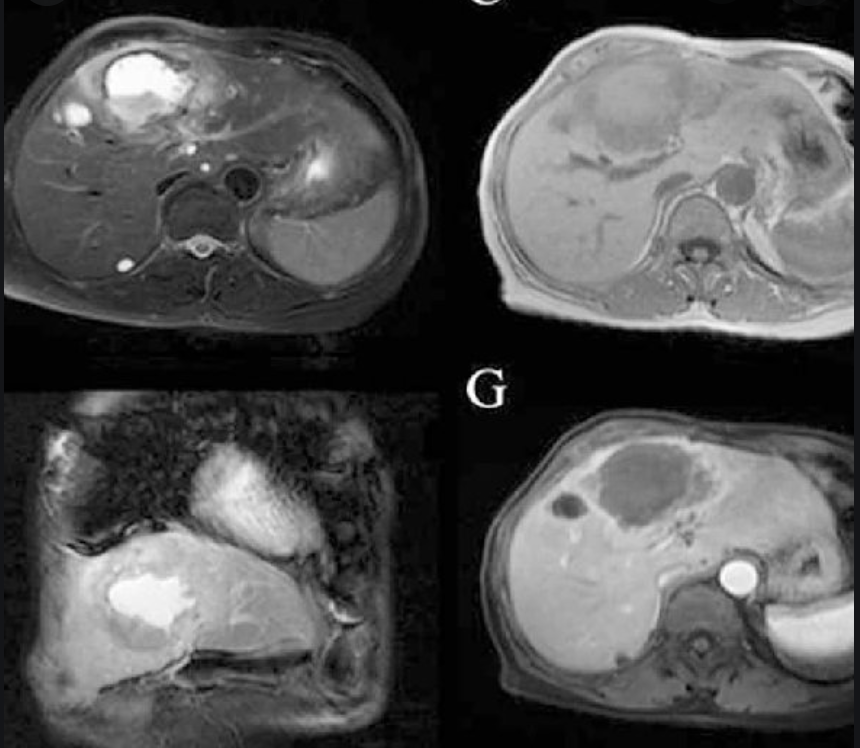

MR-4

MR: T2 central hyperintensity, irregular wall that enhances late, perilesional enhancement.